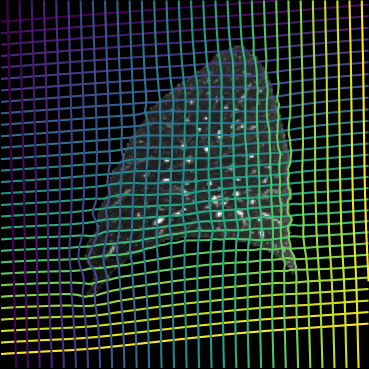

Inverse consistent rigid, affine, nonparametric, and MLP registration. We train networks on MNIST 5s using the methods in Secs. 3 and 4, demonstrating that the resulting networks are inverse-consistent. Our TwoStepConsistent (TSC) operator can be used on any combination of the networks defined in Sec. 3. For demonstrations, we join an MLP registration network to a vector field registration network, and join two affine networks to two vector field networks. Fig. 2 shows successful inverse-consistent sample registrations.

| Moving Image | Warped Image | Fixed Image | Moving Image | Warped Image | Fixed Image |